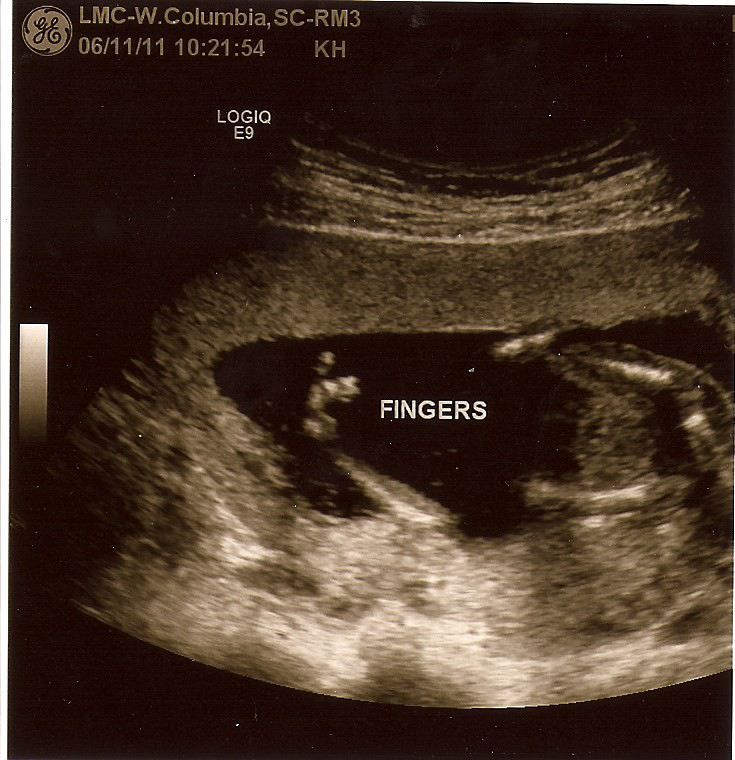

This weekend I went back found another round of fun at seventeen weeks. The hubs didn't come along this time and he sure missed out on some laughs.

I sure was surprised when this time we saw little boy bits! So much for pink and sparkles haha. Luckily we hadn't purchased anything yet, but being the cautious man he is, the hubs still wants to wait incase the boy bits turn back into girl bits. I guess we will see what happens the next time.